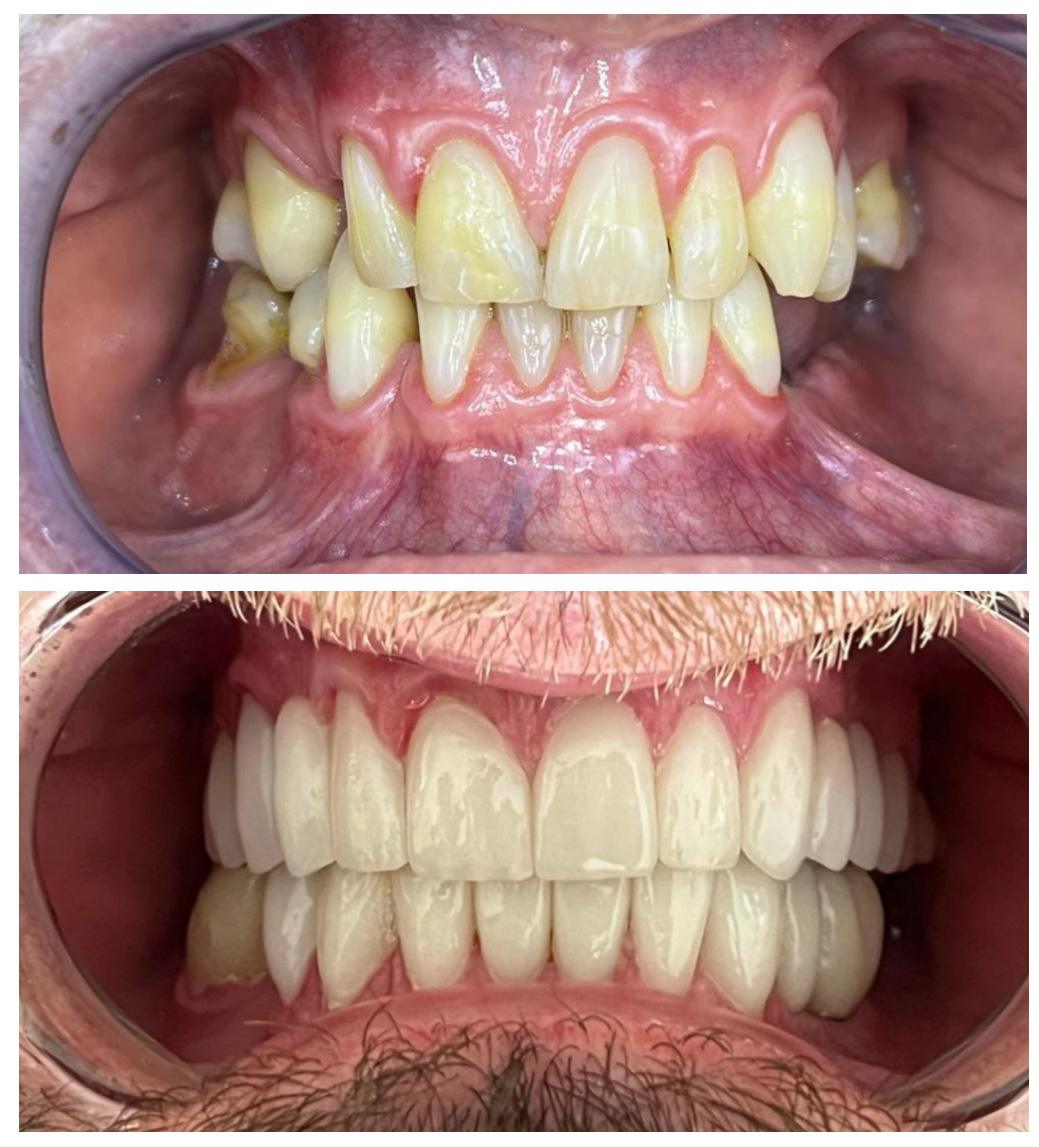

Lek. stom. Michał Badowski

Pacjentka zgłosiła się do naszej Kliniki, gdyż od zawsze marzyła o zdrowym i pięknym uśmiechu.

Pod kierownictwem lek. stom. Michała Badowskiego po wnikliwej analizie została przeprowadzona korekta dziąseł i pozbycie się nieestetycznych koron na podbudowie metalowej, eliminując tym samym nawracające stany zapalne dziąseł.

Następnie została wykonana wizualizacja nowego uśmiechu, idealnie dopasowana do twarzy Pacjentki. Po jej akceptacji, przygotowaliśmy komplet koron i licówek pełnoceramicznych na górne i dolne zęby.

Całe leczenie trwało zaledwie 3 miesiące!

Dzięki współpracy lek. stom. Michała Badowskiego i techn. dent. Joanny Gancarz z laboratorium Dentalscan Pacjentka zachwyca pięknym uśmiechem!